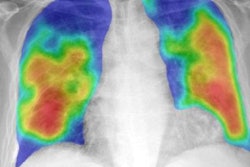

The MAIL2.0 AI model provides a probability score of 0 (low probability of COVID-19) to 1 (high probability) after analyzing chest radiographs. In this radiograph of a COVID-19 case, the model's probability score of 0.985 indicated a high probability of having the disease. Image courtesy of Dr. Michael Kuo.The model significantly outperformed the radiologists (p < 0.001). Delving further into the results, the researchers found that the MAIL2.0 model correctly identified 40 (81.6%) of the 49 COVID-19-positive cases that were missed by the radiologists. On the other hand, the radiologists spotted two (18.2%) of the 11 COVID-19-positive cases that the model had missed.